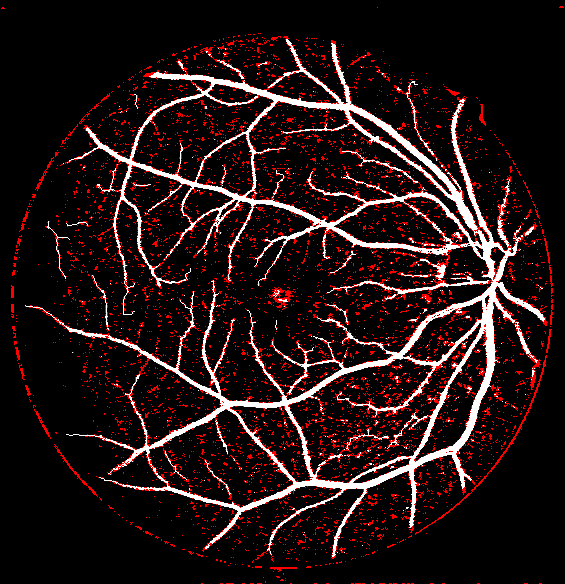

Refer to caption Refer to caption Refer to caption Refer to caption

(a)                                                                          (b)

(c)                                                                          (d)

Figure 9: Ground truth (left) and segmentation result (right): (a) and (b) are the images from DRIVE dataset, (c) and (d) are the images from the STARE dataset

V-B Vessel Segmentation Performance

The segmentation performance of the proposed model on three public available datasets is given in Table IV. It can be observed that the proposed model can achieve more than 95%percent9595\% segmentation accuracy on the DRIVE, STARE and CHASE_DB1 datasets, with the highest accuracy score Acc=96.0%𝐴𝑐𝑐percent96.0Acc=96.0\% achieved in the DRIVE dataset. Some exemplary segmentation results are shown in Fig.9. When treating the unknown regions as background regions, AUC=0.833 of trimap is 2.6%percent2.62.6\% lower than the proposed model while Acc of trimap is similar to the proposed model. In addition, Se=0.679𝑆𝑒0.679Se=0.679 of trimap is 5.7%percent5.75.7\% lower than the proposed model. These observations show that trimap can already have good segmentation performance, which indicates that the selection of region features is very effective in segmenting blood vessels. From Table IV, it can be observed that the model with vessel skeleton extraction can achieve more than 5%percent55\% increase of Sensitivity𝑆𝑒𝑛𝑠𝑖𝑡𝑖𝑣𝑖𝑡𝑦Sensitivity and 2%percent22\% increase of AUC𝐴𝑈𝐶AUC compared with the model without vessel skeleton extraction while Acc𝐴𝑐𝑐Acc of the model with vessel skeleton extraction is similar to the model without vessel skeleton extraction, which demonstrates the effectiveness of vessel skeleton extraction.